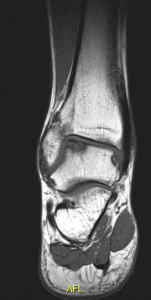

De orthopedisch chirurg zal beslissen of bijkomende onderzoeken nodig zijn (RX, MRI, arthro-CT, SPECT-CT). De grootte, diepte en lokalisatie van een kraakbeenletsel bepalen de behandeling. Een pijnlijk kraakbeenletsel bij de volwassene dient met een ingreep behandeld te worden. Bij kinderen kan een afwachtende houding aangenomen worden, tenzij het bot- kraakbeen-fragment dreigt los te komen: dan is fixatie nodig (of verwijderen als het helemaal is losgekomen).

Grote kraakbeen defecten dienen soms via andere technieken aangepakt te worden. De twee meest toegepaste chirurgische behandelingen bij een groot osteochondraal letsel in de enkel (meestal de talus of sprongbeen), zijn een OATS-procedure en een AMIC-procedure.

Bij een OATS-procedure wordt een cilinder bot- en kraakbeen uit de knie (of enkel zelf) geboord, om dan getransplanteerd te worden in het kraakbeen defect in de enkel. Dit is een veel gebruikte techniek met prima resultaat.

Bij een AMIC-procedure wordt het kraakbeen- en botdefect opgevuld met eigen bot, waarna er een kunststof membraan wordt opgelijmd. Dit laat toe dat stamcellen uit het beenmerg zich in deze membraan nestelen en zich transformeren tot nieuw kraakbeen. Vandaar de (engelse) benaming: Auotologous Matrix-Induced Chondrogenesis. Het grote voordeel is dat deze techniek eenvoudig(er) is: er is geen ingreep ter hoogte van de knie nodig, en slechts zelden een osteotomie van de enkel nodig (binnen- of buitenenkel loszagen om voldoende ruimte in de enkel te creëren om deze techniek toe te passen). De resultaten van een AMIC-procedure zijn excellent.